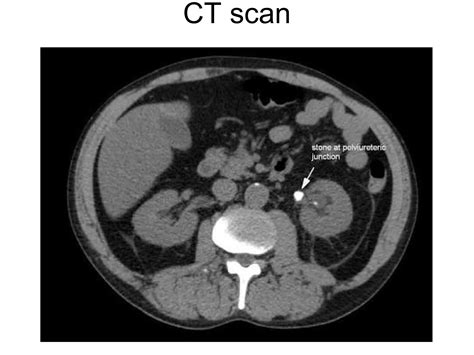

Kidney Stones Severe, sharp, wave-like pain CT Scan or Ultrasound